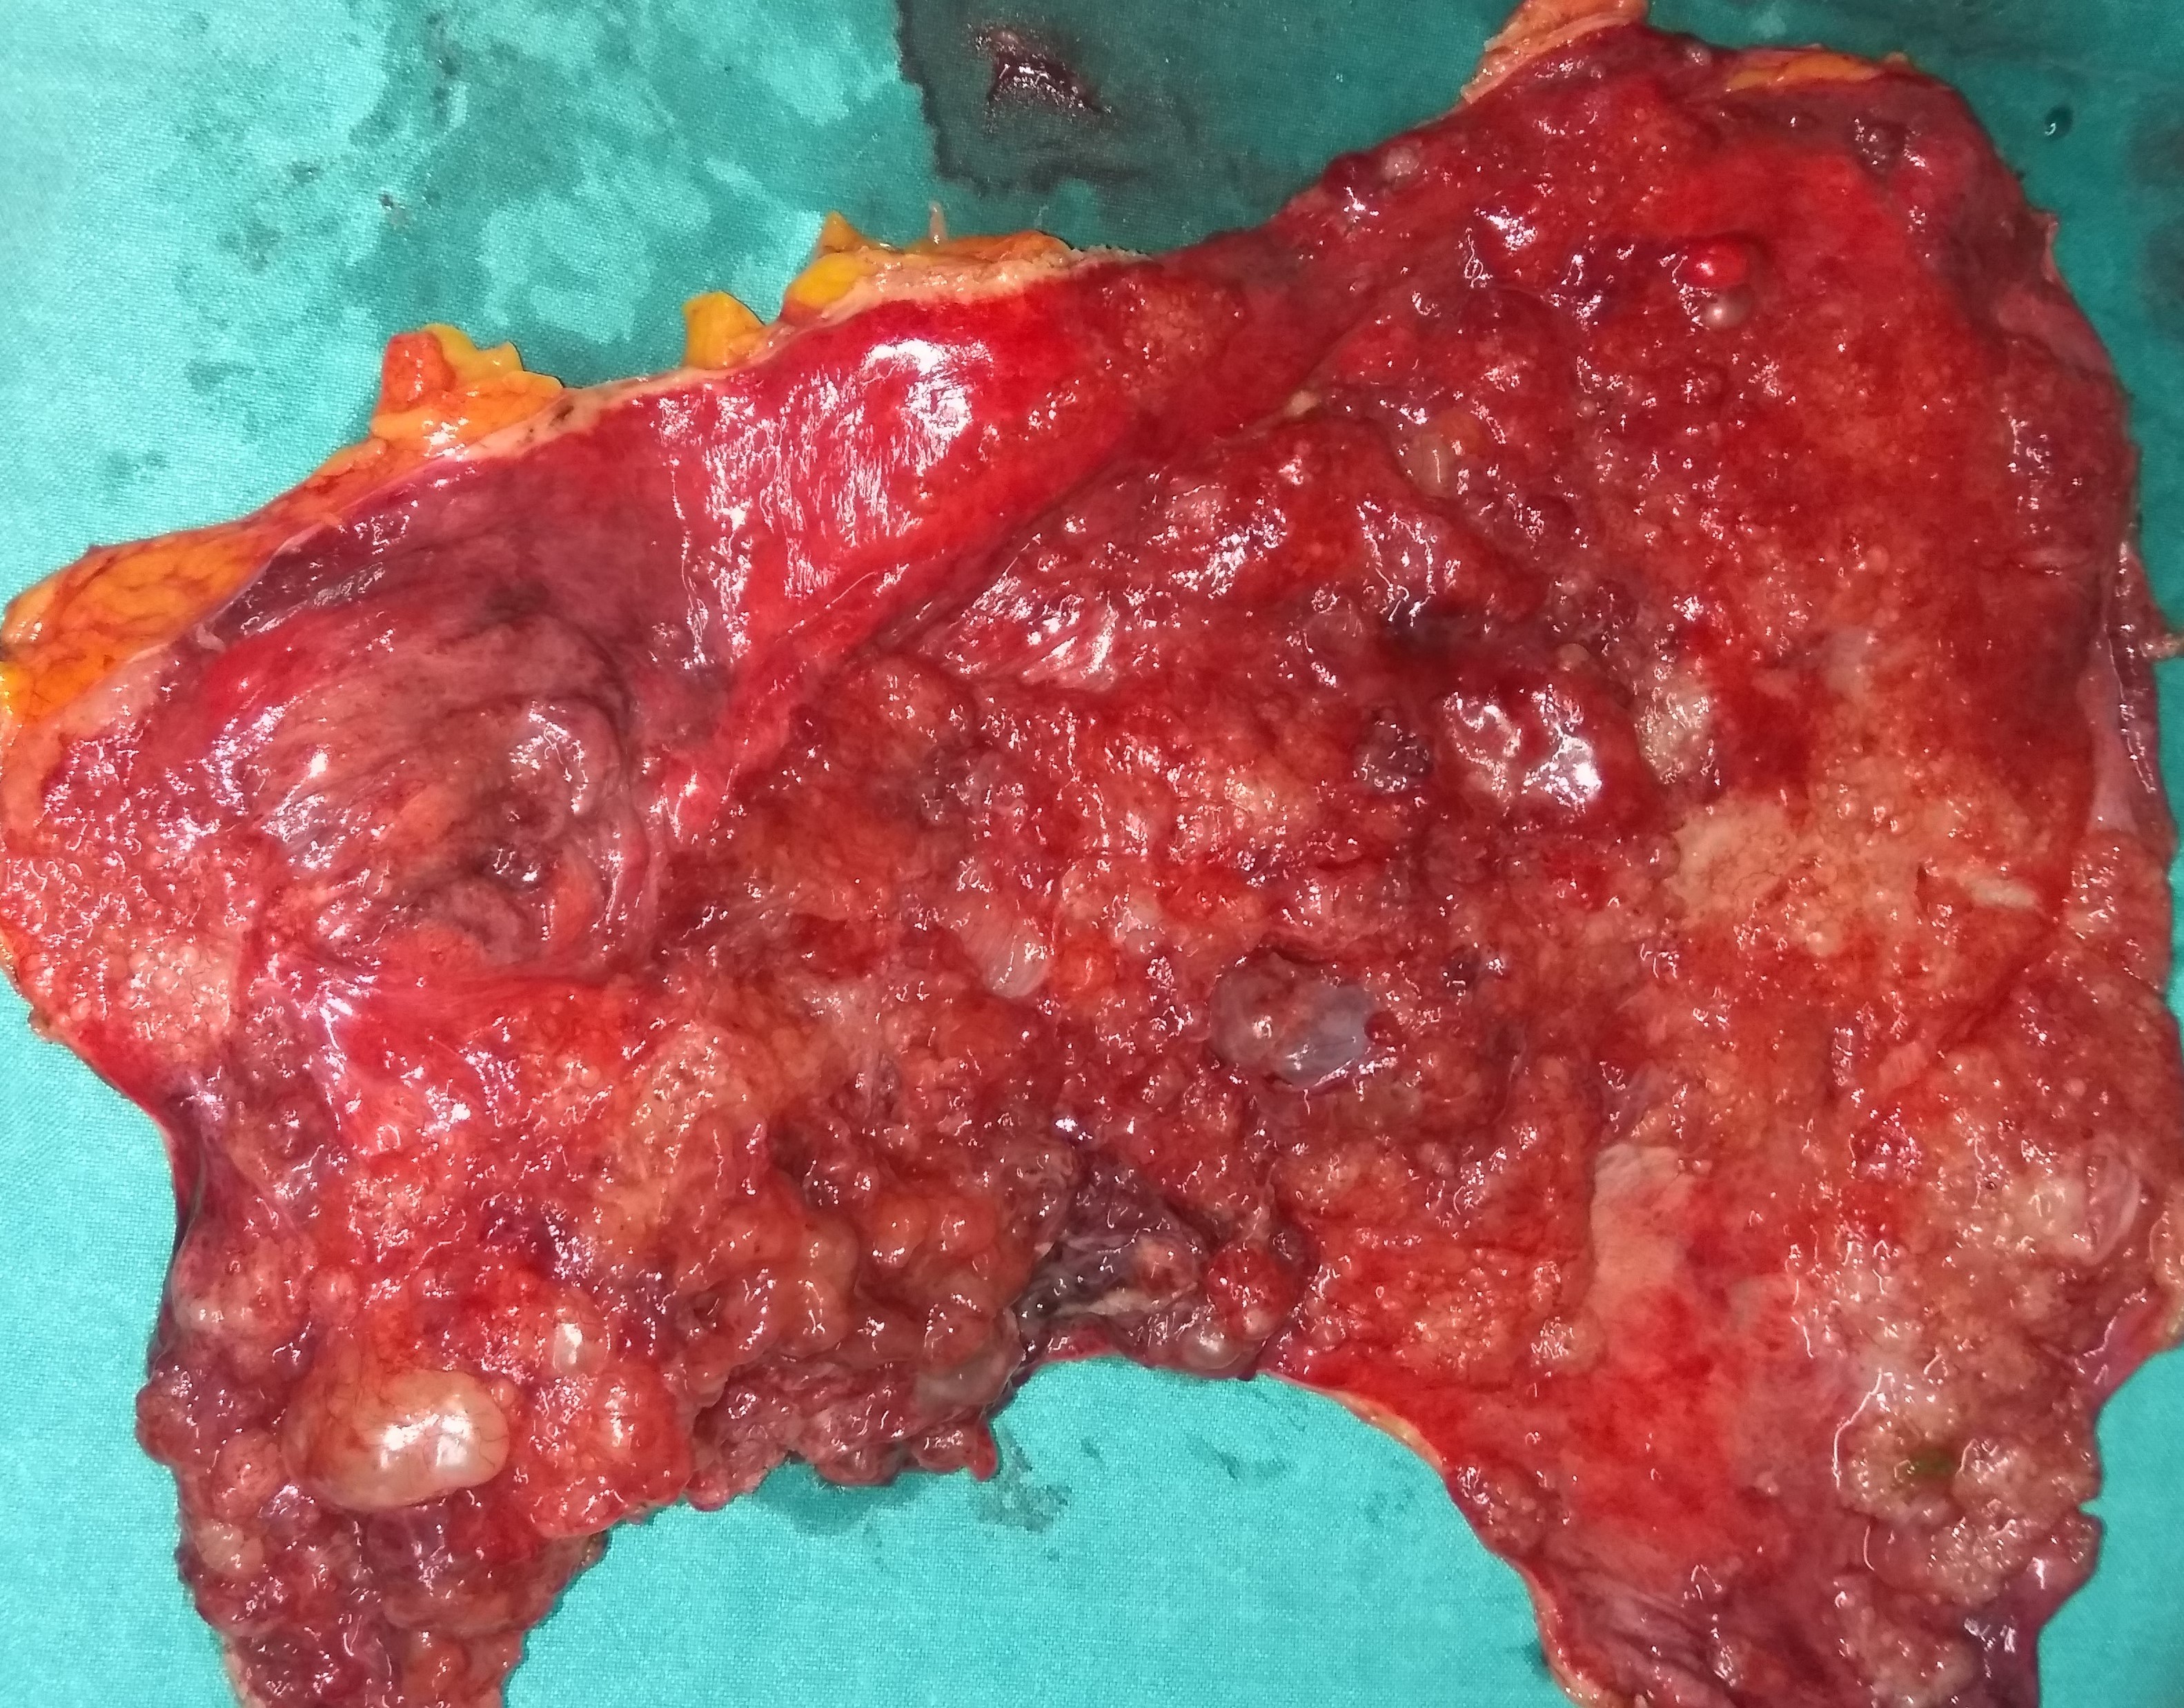

Σχήμα 2 . Μακροσκοπική άποψη του ινομυξοειδούς σαρκώματος που αφαιρέθηκε (ευγενική παραχώρηση Δρ. Β. Πενόπουλος) .